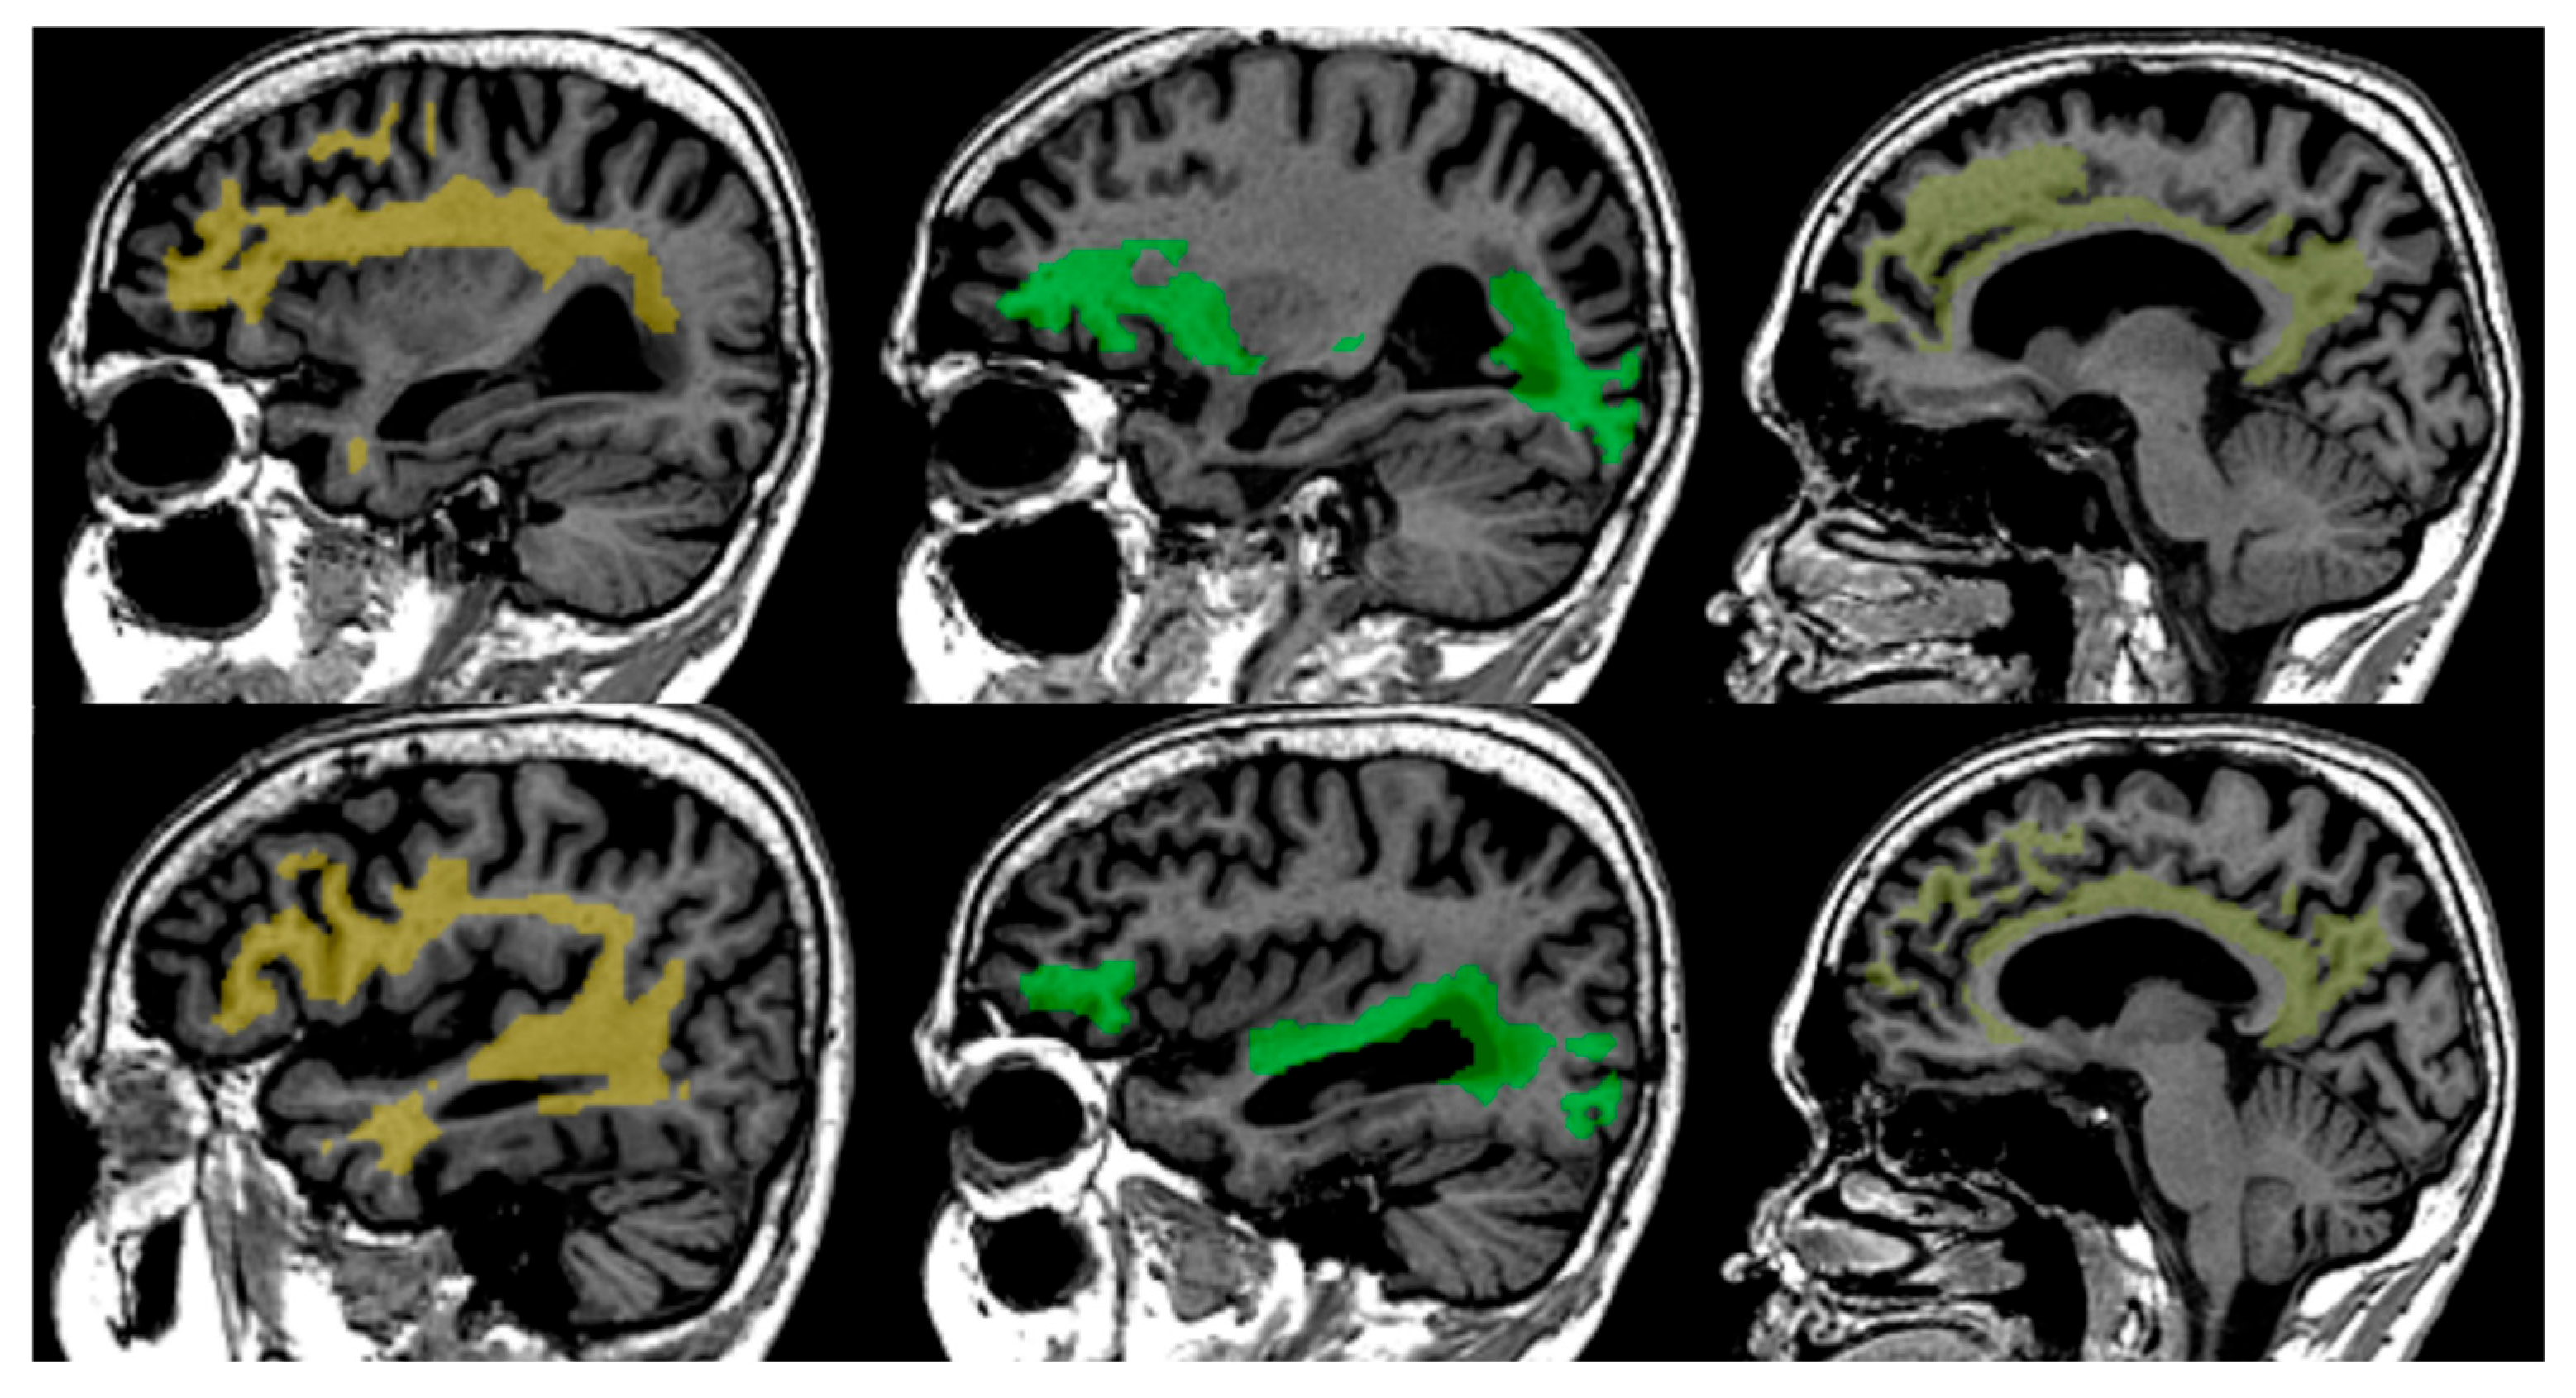

Performed steps for processing included eddy current correction with affine registration, the use of Tractseg (see Figure 1) for creating a binary tract mask [21], and then computing the mean FA from iteratively reweighted linear least squares in the tract mask [22]. Further, FA maps and distributions are calculated and extracted from the region of interest. After preprocessing, the resulting FA data are standardised, harmonised, and compared to age- and gender-normative data obtained from a healthy population database that consists of 918 MR studies from 788 unique patients aged from 18 to 86 years, acquired on different scanners and equally distributed over different age groups [23,24,25].

Figure 1.

Tract segmentation using TractSeg from T1 images from left to right—Superior Longitudinal—Arcuate Fasciculus (SLF-A, bright yellow colour), Inferior Fronto-Occipital Fasciculus (IFO, green colour), Cingulum (Cin, light yellow colour).